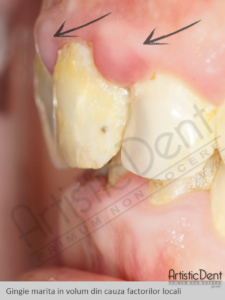

Ca orice tesut traumatizat, gingia va incerca sa se apere fie prin retractie gingivala cauzand noi probleme dentare, fie prin crestere in volum( gingia umflata).

7.Gingia marita in volum sau tumefactia gingivala este, de obicei, un semn principal ce ne indica inflamatia gingiei si apare prin actiunea factorilor locali microbieni si iritativi (placa bateriana, tartru, carii dentare etc.), dar si ca o consecinta a factorilor generali (gingia tumefiata din diabet si sarcina, cresterea gingivala din tratamentul epilepsiei si a afectiunilor cardiace etc.)